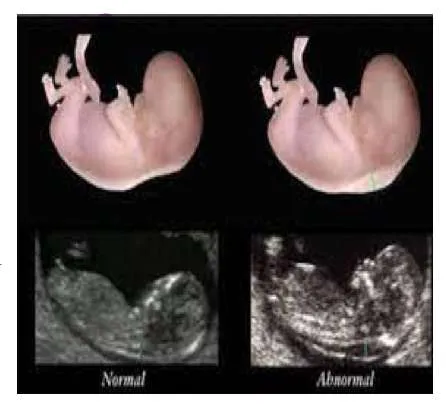

A 23-year-old primigravida presented for her antenatal care follow-up. She is in her 28 weeks of pregnancy. She didnโt have any symptoms except for mild dyspepsia.

Procedure indicated if needed

Administer anti D immunoglobulin if indicated.